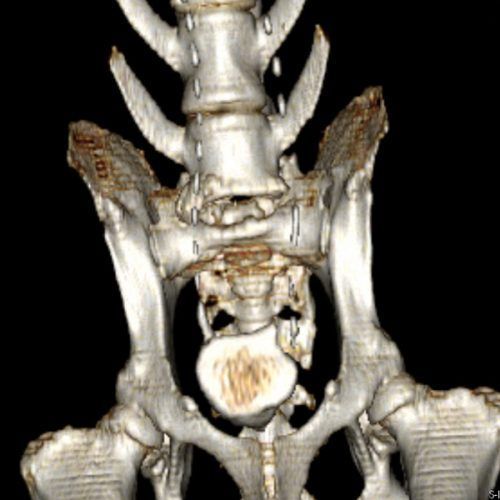

TC MULTISTRATO